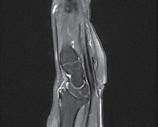

CT-ul cu reconstrucție tridimensională sau RMN genunchi relevă mult mai

bine complexitatea fracturii și dau posibilitatea unui planning preoperator superior estimării radiologice clasice(7). CT-ul este mai rapid și mai ușor de făcut, dar RMN decelează mai bine leziunile de menisc sau ligamentare.

Schatzker III, Osteosinteză cu șuruburi percutană

Schatzker VI, Reducere sângerândă și osteosinteză cu 2 plăci